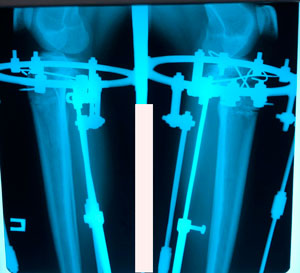

5 ый ень круток

IMG_3326-24-05-19-12-52.JPG